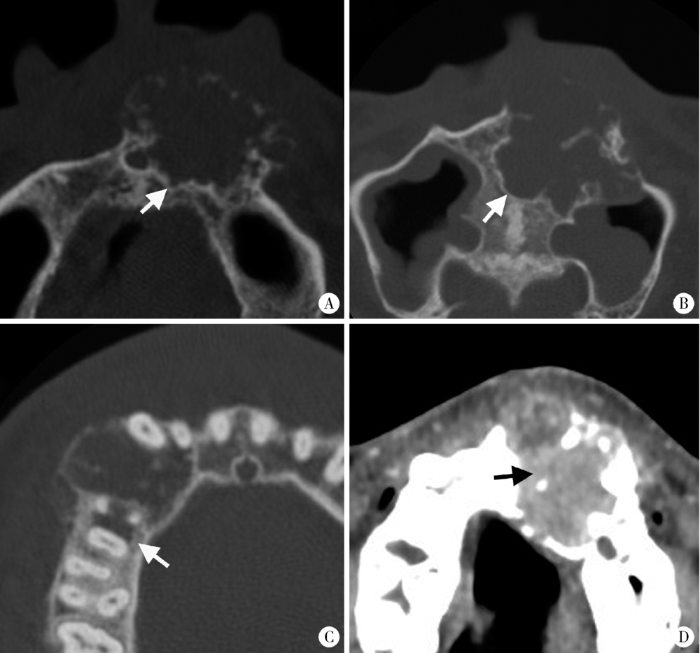

促结缔组织增生型成釉细胞瘤成骨致密型(Ⅰ型)

Figure 2

The densely ossifying DA (type Ⅰ)

CT images shows the internal ossifications appear like bone trabecular (white arrow, A) or densely ossification (white arrow, B).

促结缔组织增生型成釉细胞瘤蜂窝/皂泡型(Ⅱ型)

Figure 3

The honeycomb/soap bubble type of DA (type Ⅱ)

Axial CT images shows the scattered inhomogeneous ossifications appearing as honeycomb (white arrows) or soap bubbles (black arrows).